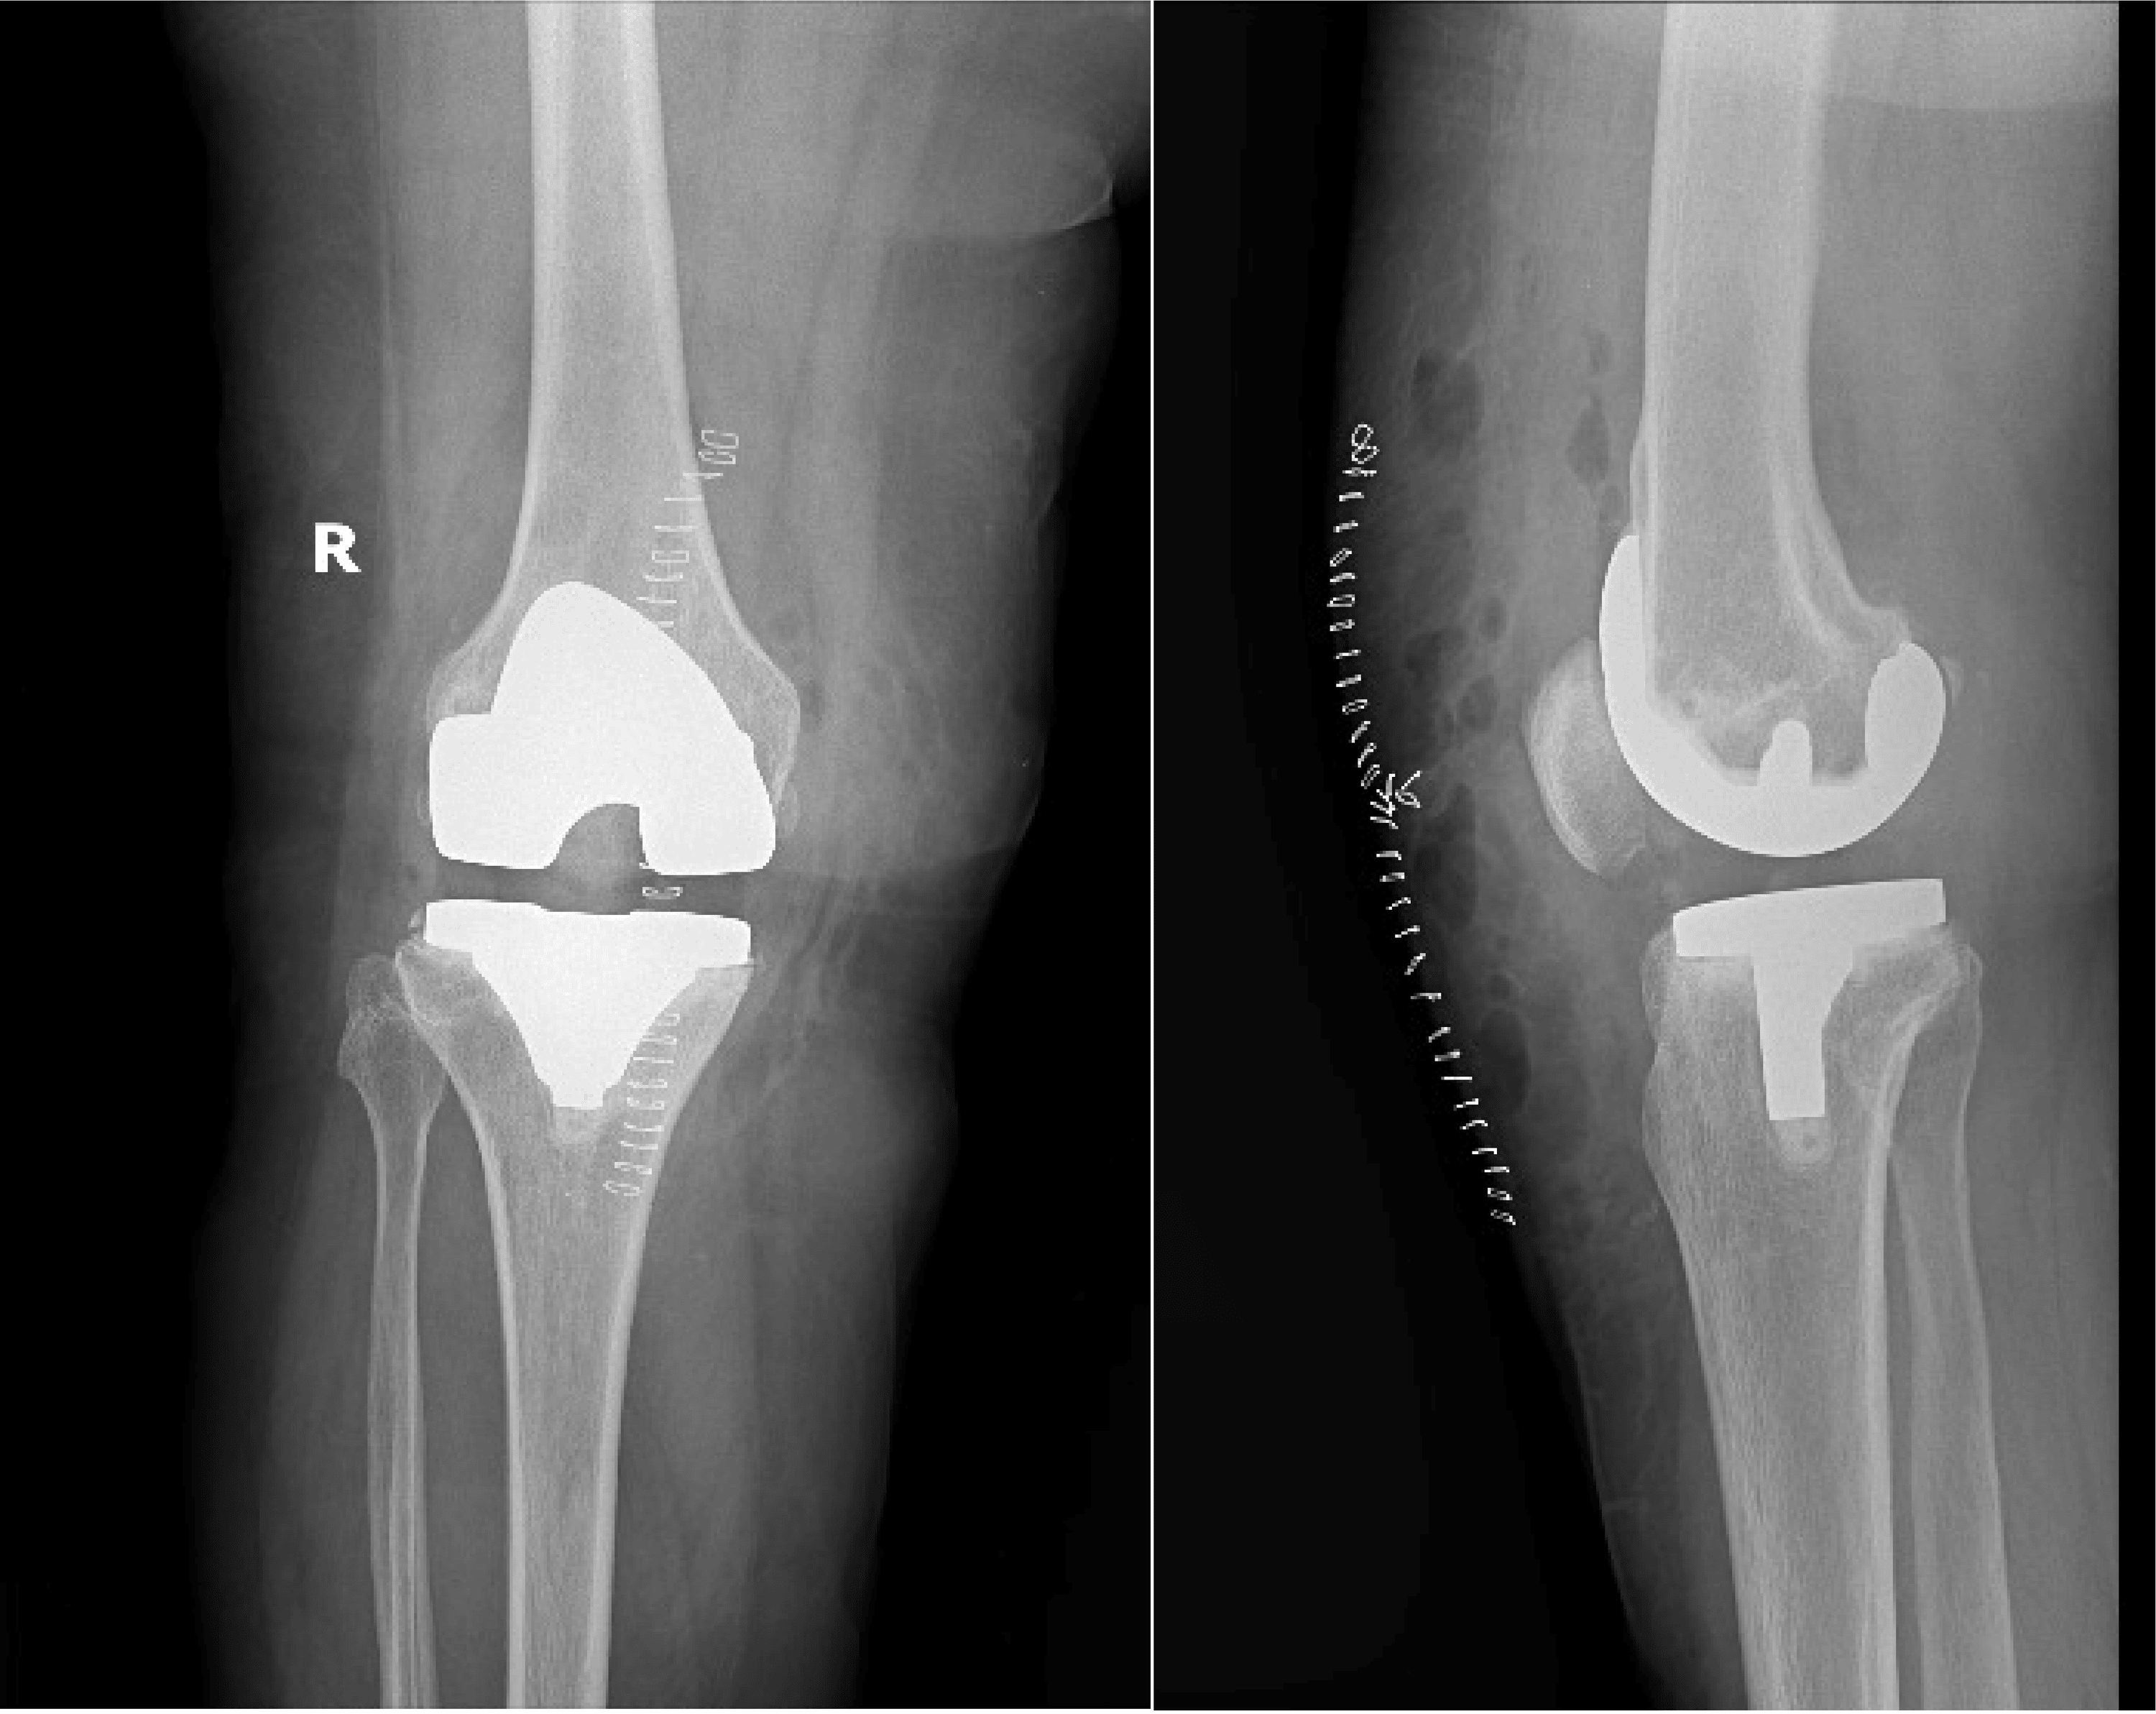

Post Knee Replacement Complications . each person’s individual risk of developing complications after knee replacement surgery is different. Some people who have knee replacement surgery still experience pain. However, it's possible that you may have ongoing. what are potential complications of a knee replacement? Most periprosthetic fractures occur in the femur (thigh bone), above a total knee replacement. the most common reason for knee replacement surgery is to ease pain caused by arthritis. most people find their daily life improves after a knee replacement.

Most periprosthetic fractures occur in the femur (thigh bone), above a total knee replacement. what are potential complications of a knee replacement? However, it's possible that you may have ongoing. Some people who have knee replacement surgery still experience pain. each person’s individual risk of developing complications after knee replacement surgery is different. the most common reason for knee replacement surgery is to ease pain caused by arthritis. most people find their daily life improves after a knee replacement.